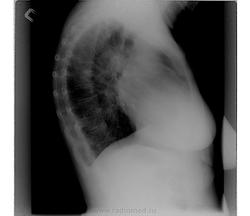

Написал бы то, что видно: Р-признаки эмфиземы легких (диафрагма опущена, уплощена, наличие легочной "талии"), артериальной гипертензии в малом круге кровобращения (выбухает 2 дуга по левому контуру сердечной тени, корни расширены за счет сосудов); "метелка" в области головки левого корня провоцирует размышления на тему центрального рака. Ну, и еще раз уточнил бы паспортные данные, не похоже на 46 лет (ксерокс паспорта или полиса ОМС обычно лежит в кармашке истории болезни).

Кифосколиотическая деформация грудной клетки; легочная гипертензия. Возможно, переснять "ровнее" не удастся. Думаю, скиалогический возраст пациентки и неправильную укладку можно объяснить деформацией грудной клетки, как минимум, "с юности". Группа инвалидности по бронхиальной астме тоже с юности? Знание анамнеза помогло бы уточниться с анализом рентгеновского архива.

Андрей Юрьевич, добрый вечер! имхо: выбухание 2 дуги по левому контуру сердца, скорее всего из-за установки при съёмке. Может быть и не стоит говорить об эмфиземе лёгих т.к.нет расширения ретростернального пространства (а, "лёгочная талия" вероятно отять же, за счёт укладки (поворот).О лёгочной гипретезии можно достоверно говорить , только после проведения эхокардиографии, по признаку разницы градиентов давления в лёгочной артерии.

Написал бы то, что видно: Р-признаки эмфиземы легких (диафрагма опущена, уплощена, наличие легочной "талии"), артериальной гипертензии в малом круге кровобращения (выбухает 2 дуга по левому контуру сердечной тени, корни расширены за счет сосудов); "метелка" в области головки левого корня провоцирует размышления на тему центрального рака.